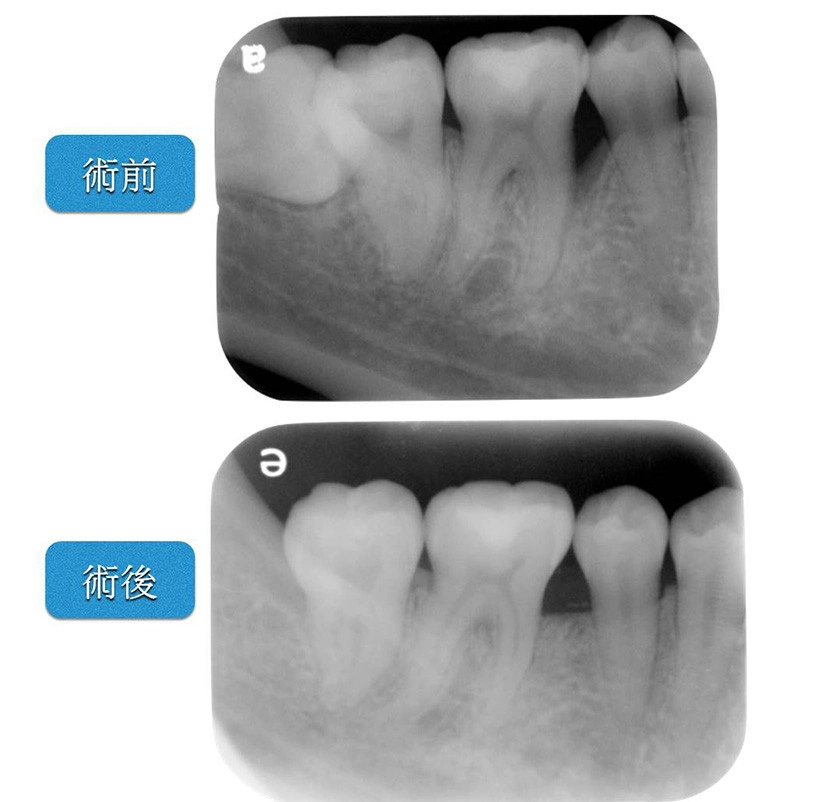

牙周再生手術